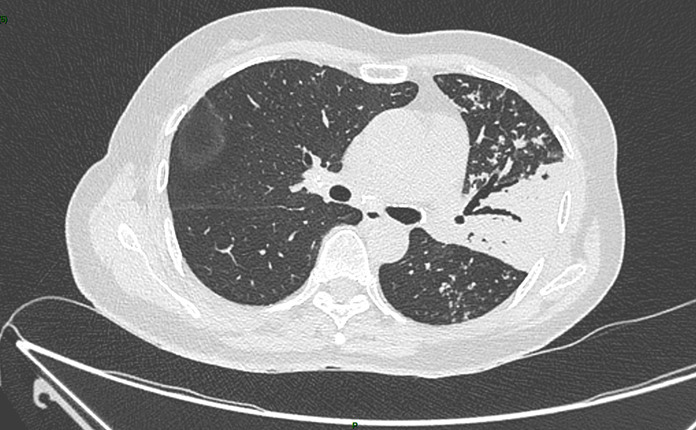

Un scanner thoracique est finalement réalisé devant cette toux chronique et l’altération de l’état général, dont voici quelques coupes :

Figure 5 (Jacques Durin, La Revue du Praticien)

Aspect de pneumopathie avec une condensation lobaire supérieure gauche et la présence d’un bronchogramme aérien dessinant l’arbre bronchique (flèche jaune).

Absence de liquide au contact de la condensation, pas de pleurésie déclive.

Le compte-rendu de radiologie décrit un aspect de pneumopathie lobaire supérieure gauche associée à des micronodules péri-bronchiolaires et des adénopathies médiastino-hilaires calcifiées.